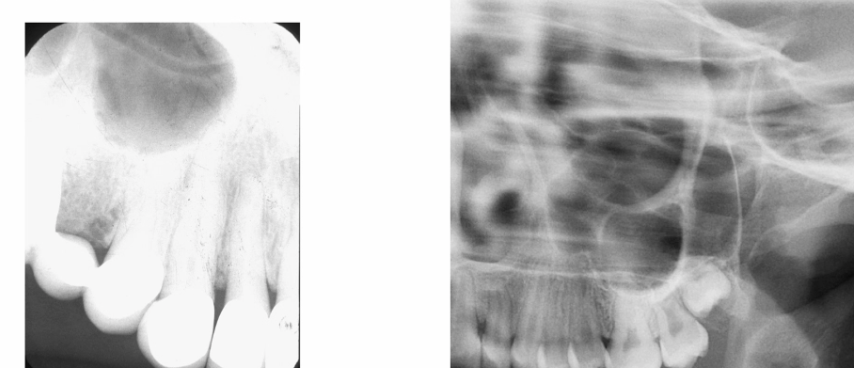

what is this?

a dentigerous cyst

- a cyst forming around the crown of an unerupted tooth

- always forms from the CEJ of the tooth and follows the outline of the crown